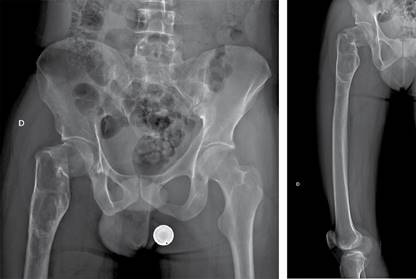

Se realizaron radiografías de pelvis y de fémur, que revelaron una fractura basicervical de fémur derecho Garden II Pauwells III AO 31B2.3r, con un patrón lítico de destrucción geográfica y un margen esclerótico bien delimitado que se extendía hacia el fémur distal aproximadamente 14 cm, sin evidencia de reacción endóstica o perióstica (Figura 1). Estas imágenes eran compatibles con una lesión de lento crecimiento, que necesitaba confirmación mediante histopatología, ya que, como se mencionó previamente, a pesar de que el paciente cuenta con antecedente de DF, existen otras entidades, algunas de comportamiento biológico maligno, de las cuales debe hacerse diagnóstico diferencial. Como estudio complementario, se realizó una tomografía simple de fémur derecho, ya que nos permite delimitar perfectamente los bordes de la tumoración para la planeación quirúrgica, así como precisar el patrón de destrucción lítico y el adelgazamiento del hueso cortical (Figura 2). Los parámetros del metabolismo óseo se encontraban dentro de valores normales.

Figura 1: Radiografías anteroposterior de pelvis y anteroposterior de fémur en las que se observa fractura a nivel del cuello femoral, basicervical en terreno patológico con un patrón lítico de destrucción geográfica, con margen esclerótico bien delimitado que se extiende hacia el fémur distal aproximadamente 14 cm sin datos de reacción endóstica o perióstica que sugieran malignidad.